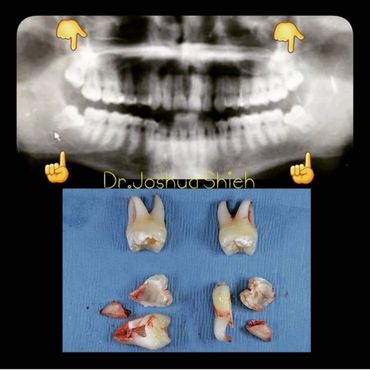

If the tooth is planned for extraction, an x-ray of the area will be taken to plan for the type of extraction.

A surgical extraction is a more complex procedure. It is used if a tooth may have broken off at the gum line or has not come into the mouth yet. Surgical extractions are commonly performed by general dentists or oral surgeons depending on the case. Sometimes it’s necessary to remove some of the bone around the tooth or to cut the tooth in half in order to extract it. For surgical extractions, patients receive local anesthetic. A suture is usually required to control bleeding and facilitate healing.

Early Wisdom Teeth Extraction

Wisdom teeth are the third set of human molars. Unfortunately, in some cases, those teeth are impacted fully or partially in bone or soft tissue and cannot erupt causing pain, discomfort and swelling. Additionally, most people have difficulty accessing these teeth during brushing or flossing causing accelerated decay and gum problems. Wisdom teeth have also been notorious for causing crowding, improper bites and pressure when they start erupting. The arrival of these late-breaking teeth can cause trouble as they are often impacted (trapped in the jawbone) because there is not enough room for them in the mouth. Our jaws are a lot smaller than those of our early human ancestors, who needed bigger jaws and more teeth for the type of food they chewed. In most people, wisdom teeth can do more harm than good and we often recommend their removal.

It can take a long time for wisdom teeth to erupt and you may not even notice the harmful effects in your mouth until you experience sudden and severe discomfort. Cramped for room, impacted wisdom teeth grow out at odd angles or remain trapped below the gums. Adjacent teeth can become prone to decay because of the unfavourable position of the wisdom teeth.

If you feel that your wisdom teeth are starting to cause problems, book an appointment to assess their condition, a panoramic x-ray will be taken and a thorough examination is conducted.